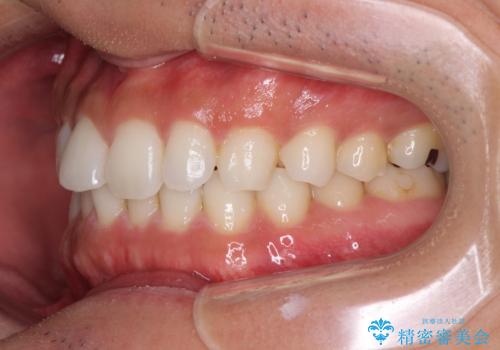

- 上下前歯のデコボコを気にして来院された患者様です。

以前矯正をした後戻りということで、歯列不正はそれほど大きくなかったため、インビザライン・ライトを用いて矯正治療を行うこととしました。

1日22時間以上しっかりと装着してくださったので、半年かからずに治療を終えることができました。